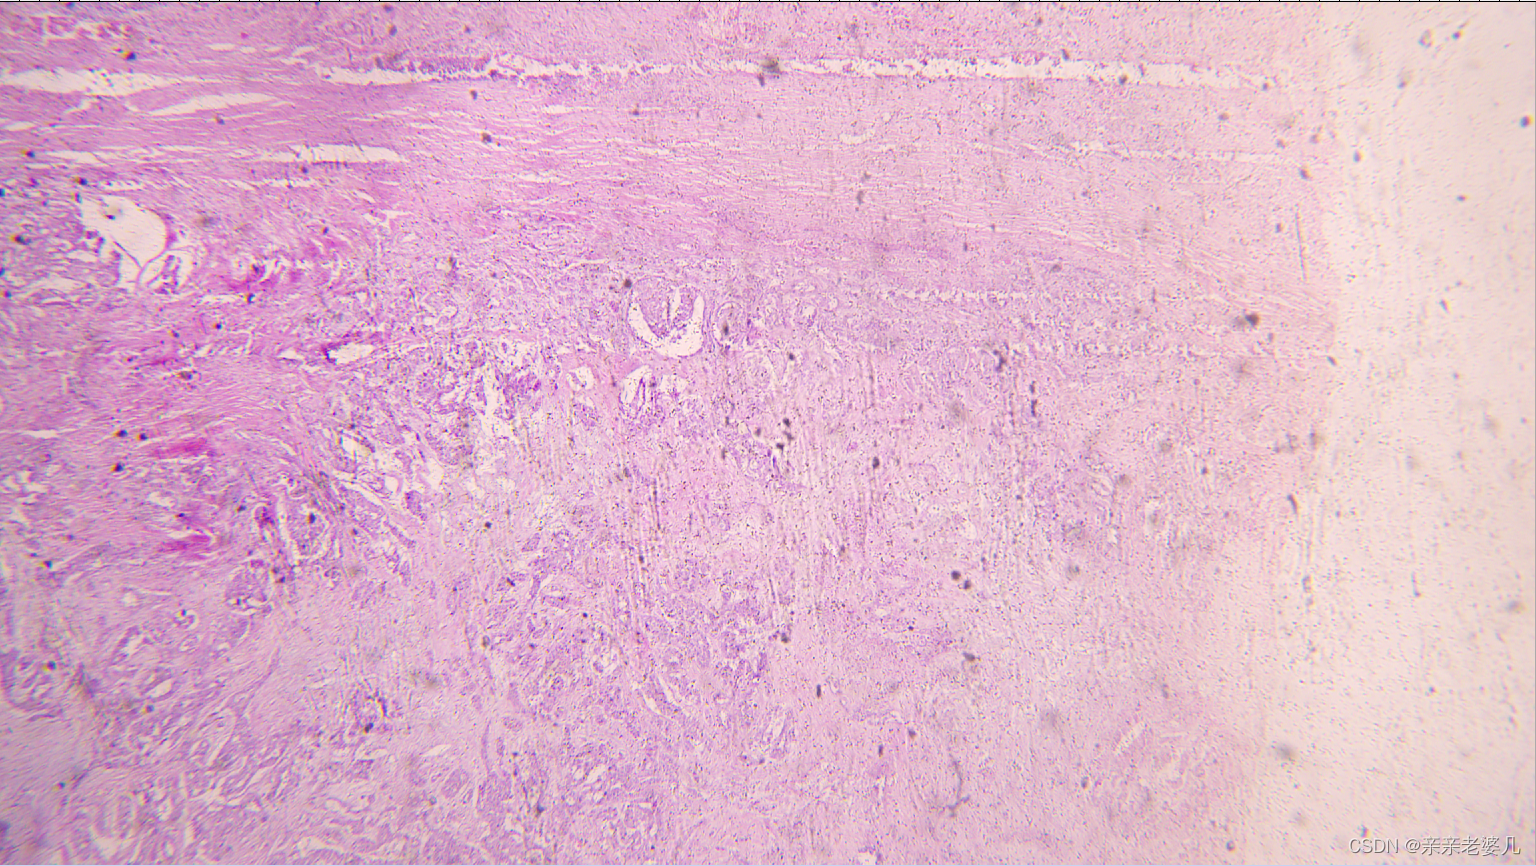

9. 千奇百怪的疾病——疾病的显微诊断及大体实物标本展示

如何获得标本:

手术 取材 包埋 蜡块 切片 染色

肠腺癌

肺水肿

肝癌

宫颈鳞癌

正常大肠

正常肺

正常肝

正常小肠